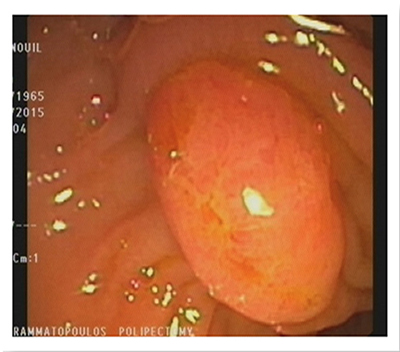

Endoscopic Removal Of Large Sessile Polyps And Submucosal Lesions

A sessile polyp is any flat wall growth without a stalk, usually detected during an endoscopic exam.

Sessile polyps differ in size, ranging from a few milliliters to several centimeters, and may be located anywhere along the digestive tract.

Our Hospital meets all these conditions. As a result, the endoscopic procedures are completely safe. Sessile polyps that are over 1 cm in size require special endoscopic management during polypectomy. A necessary condition is the submucosal injection of normal saline solution, with or without epinephrine, along with blue de methylene or indigo carmine. The infusion helps separate the mucosa and submucosa from the muscular layer. This technique also offers the endoscopy specialist the chance to understand whether they can remove the lesion. When the base of the polyp rises smoothly and easily, then it is possible to remove the polyp. The infusion may reduce the risk of bleeding and perforation following polypectomy.

Polyps that are over 2 cm in size may be removed in fragments or using the endoscopic submucosal dissection (ESD) method. Submucosal lesions are removed using a different procedure. Initially, the mucosa is lanced using a special lancet and the lesion is exposed. It is then separated from the surrounding tissue and removed.

This technique was first developed in Japan for the removal of an entire large polyp in one piece during one session.

This technique has both advantages and disadvantages.

- The anatomic pathology material (one single piece sent to histology)

- Lower risk of recurrence compared to a fragmented polypectomy